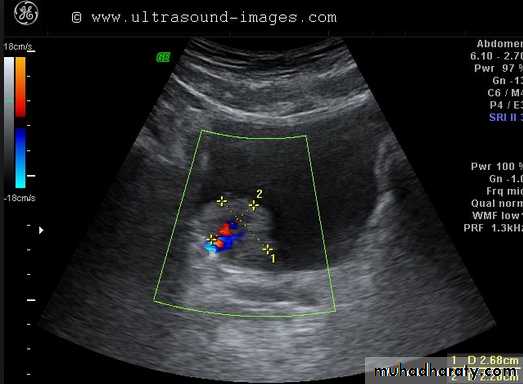

Vascular ultrasound (Doppler)

. It can yield blood flow information by applying the Doppler principle .